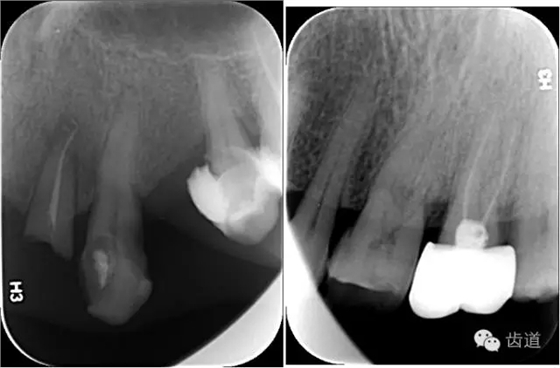

X線:根尖片、曲面斷層片(牙槽嵴頂,水平垂直吸收,程度)